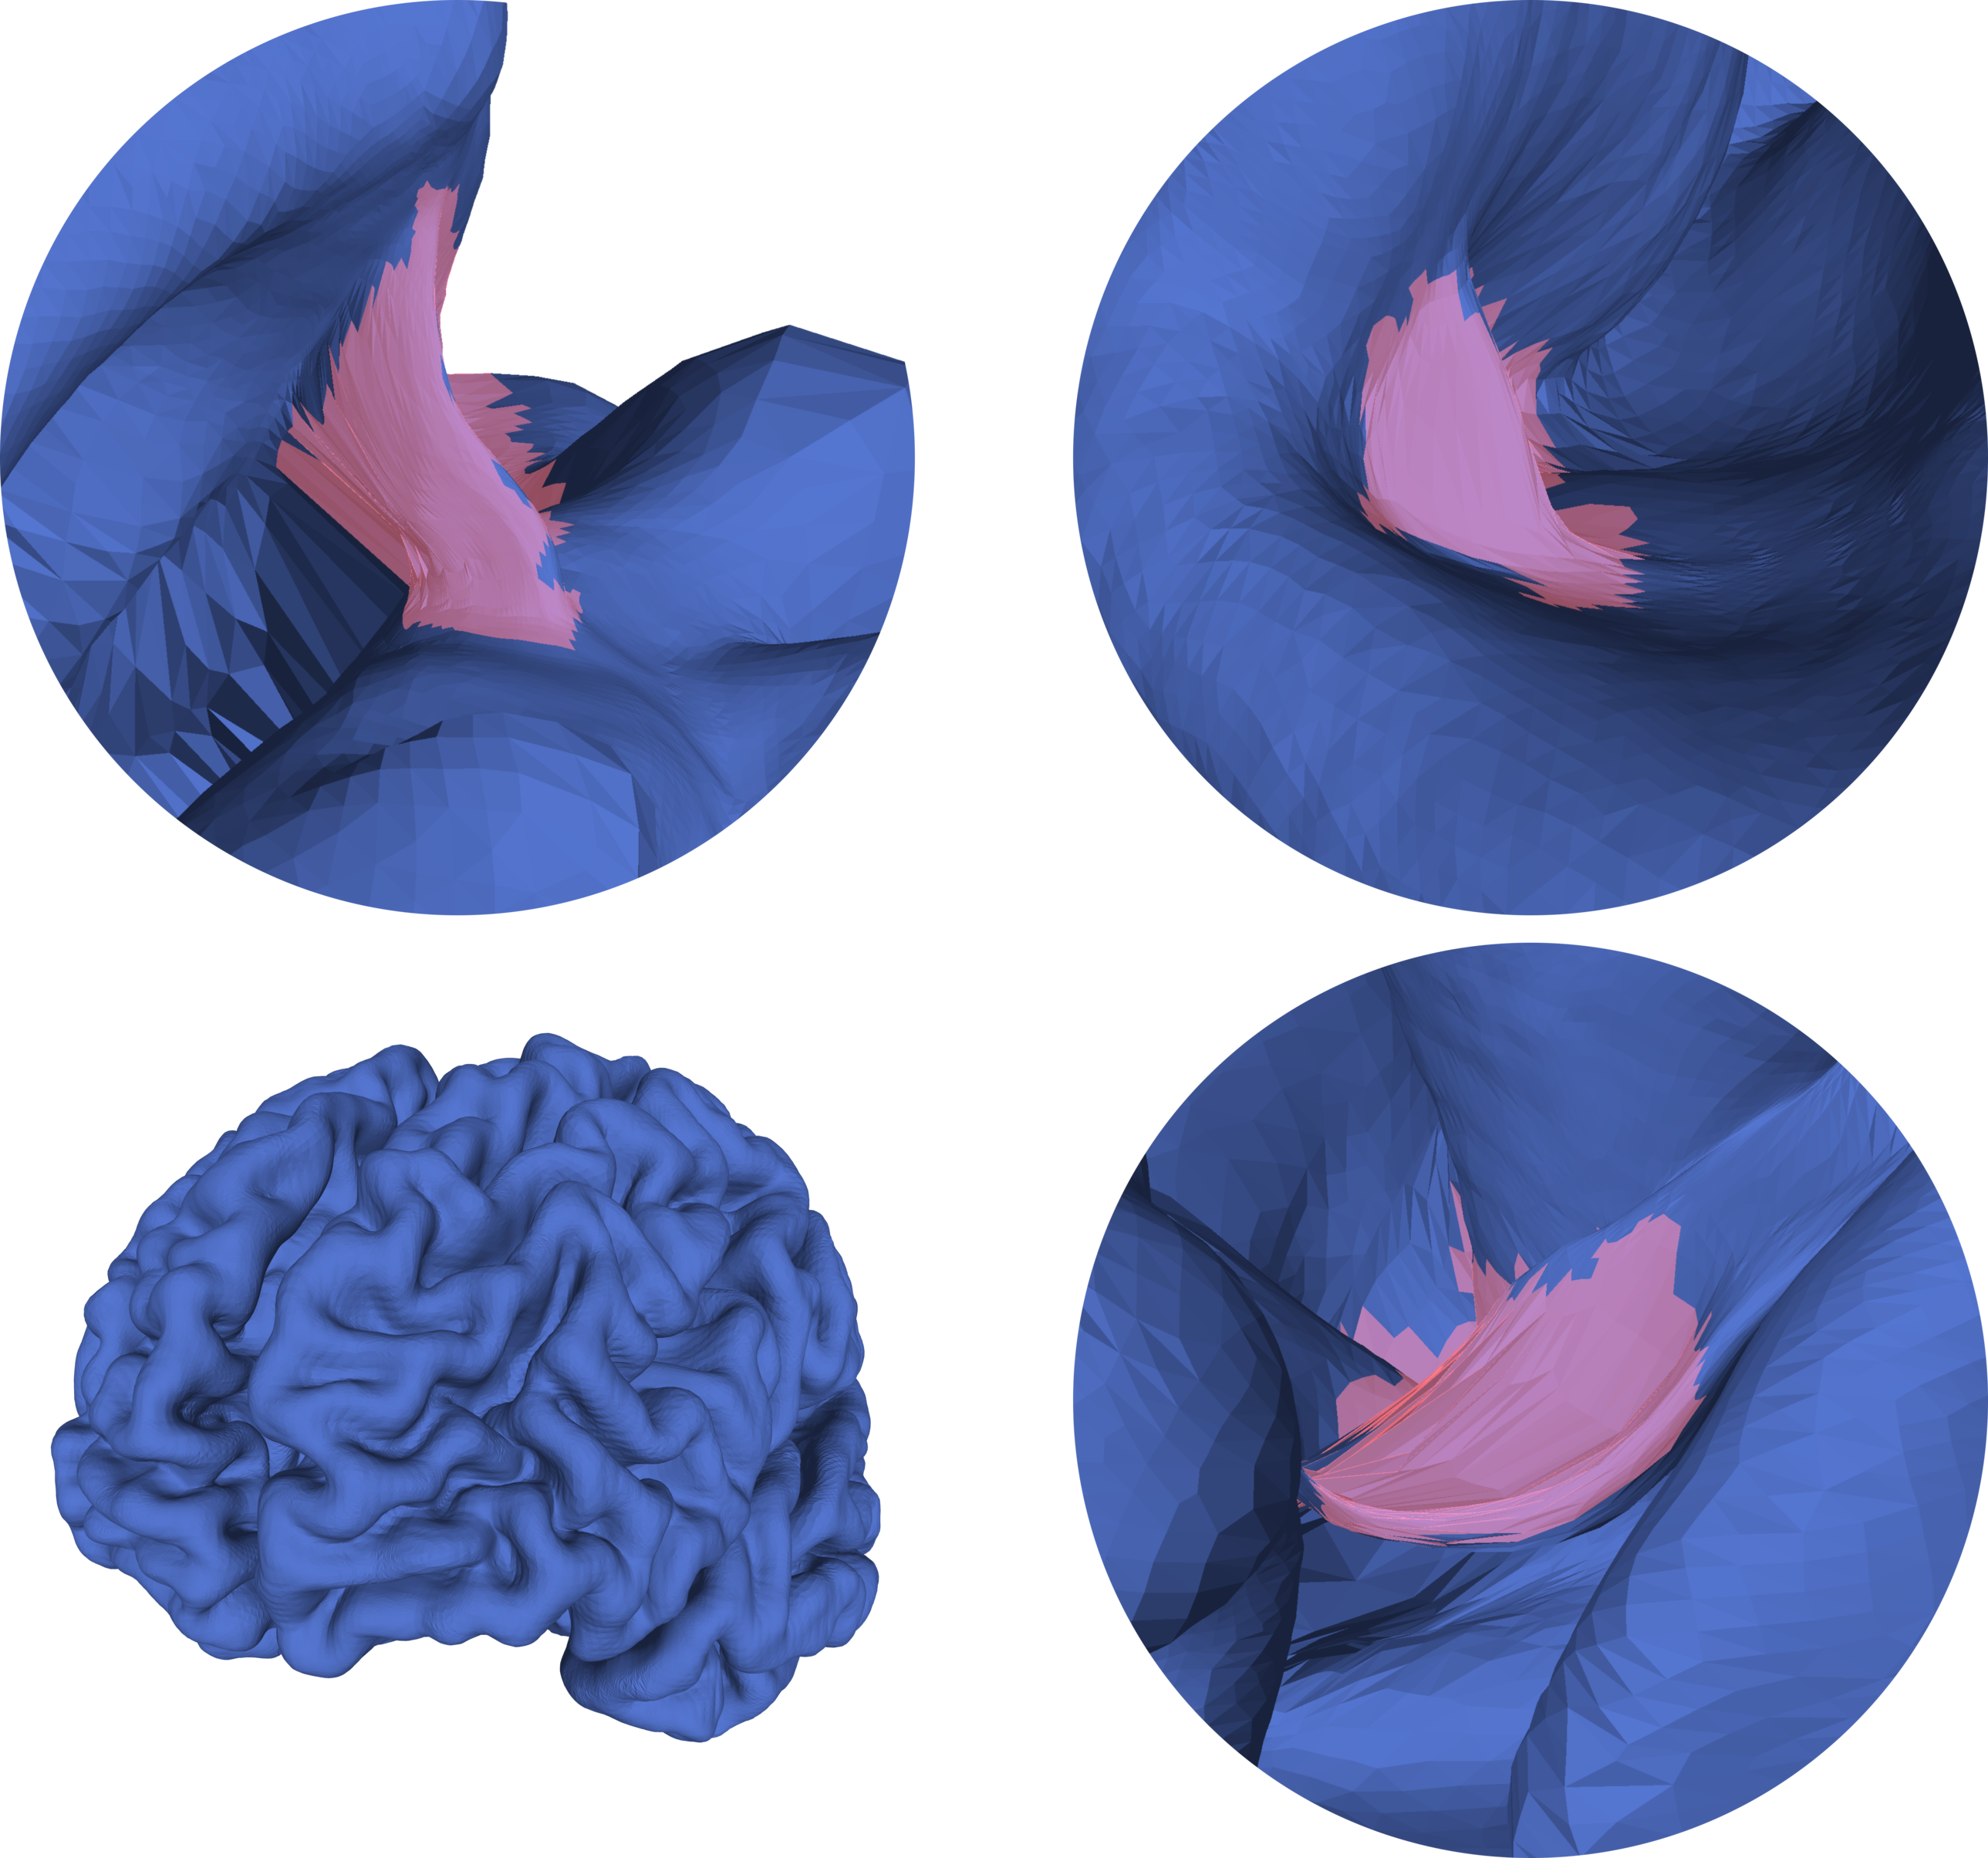

CorticalFlow’s template mesh consists of the convex-hull of all cortical surface meshes in the training set. This approach has two main shortcomings:

1. 1.

Even target surfaces with small differences between them can lead to a “loose” template. Consequently, the model has to learn “large” deformations making the smooth approximation problem harder. For pial surfaces, this problem is even worse because some template regions may lay outside the image bounds where the predicted flow field is undefined.

2. 2.

The convex-hull is defined by a set of intersecting planes which leads to sharp edges as shown in Figure 1(b). These edges are very hard to be unfolded by a smooth deformable model like CorticalFlow, because it requires non-smooth deformations with drastic local changes of direction in its flow field representation. Hence, these edges may remain in the predicted mesh as undesirable artifacts (see Figure 1(d)).

To overcome these issues, we develop genus zero smooth mesh templates that tightly wrap all training meshes. We first compute a signed distance map for every target surface mesh in the training set by computing the largest 3D bounding box that contains these meshes, create 5123superscript5123512^{3} voxel-grids into this bounding box, and populate these voxel-grids with the signed distance to each target mesh. These signed distance maps are implicit representations of the target meshes where voxels with positives values are outside of the mesh and voxels with negative values are inside of the mesh. Then, by thresholding the binary union of these maps and running the standard marching cubes algorithm [16], we obtain a template mesh that is very tight around all training surfaces. However, this template mesh looks “blocky” with many small sharp edges and undesired topological defects. The template mesh is thus smoothed using the Laplacian smoothing algorithm [10, 26] and re-meshed with Delaunay triangulation [1]. The result is a smooth template mesh with spherical topology tightly wrapping all training set surfaces (see Figure 1(c)). Finally, we apply a topology preserving mesh subdivision algorithm [2] to generate template meshes at different resolutions which are required to train CorticalFlow. Implementations of the used algorithms are available in the Libigl [12] and MeshLab [2] toolboxes.